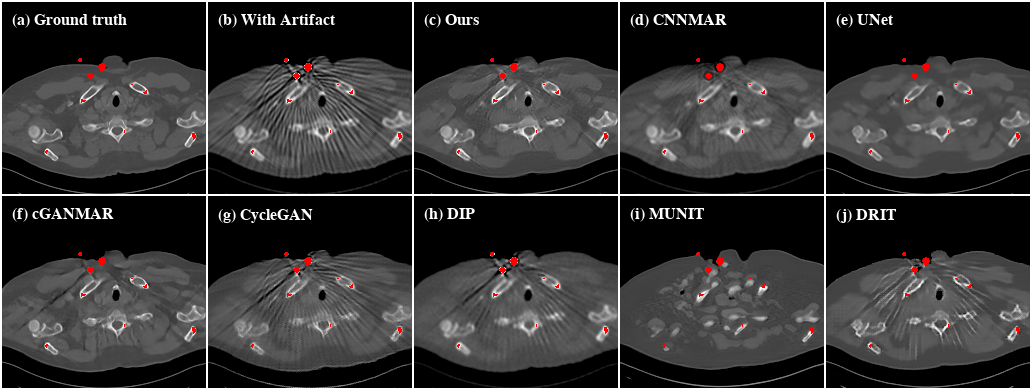

Refer to caption

Figure 8: Qualitative evaluation results of SYN. For better visualization, we obtain the metal regions through thresholding and color them with red.